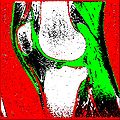

Objective 1: We have adopted a multi-contrast MR methodology to segment knee bones and cartilage structures. The algorithm utilizes tissue intensity information from multiple MR contrasts to segment structures of interest. Inputs to the algorithm included n registered MR image sets. The algorithm created an n-dimensional space of voxel intensities associated with the n image sets. The user assigned seed points to the structures of interest, and the algorithm created a cluster center for each structure of interest. Cluster radii were calculated based on standard deviations obtained from seed points, and tissue structures were classified as label maps.

• Implemented algorithm to segment structures of interest from multi-constrast MR images.

• Generated label maps of knee and hip structures.